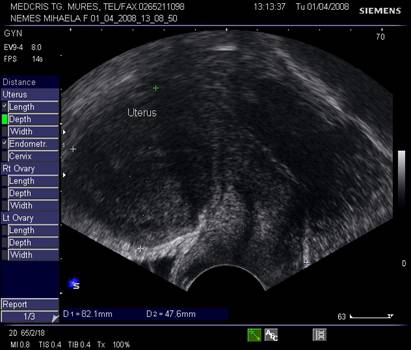

Uterul - situat intre vezica si rect, pozitia lui poate fi variabila, influentata si de umplerea vezici. De obicei, corpul uterin si colul au o relativa omogenitate interna ecografica. Cateodata imagini anecogene in peretele cervical reprezinta chiste Naboth.

Dimensiunile uterului la o pacienta nulipara matura, masurate transvaginal sunt de 7,3 cm x 4,0 cm x 3,2 cm. In general dimensiunile cresc cu paritatea si scad dupa menopauza.

Raportul intre corp si col este aproximativ de 1,6 in ceea ce priveste lungimea.[5,6]